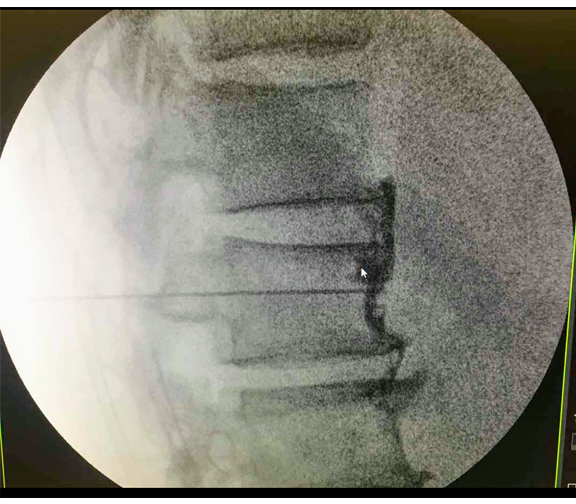

Procedimiento Bloques Simpáticos

El Sistema Nervioso Simpático está controlado por nervios llamados ganglios. Un ganglio grande, llamado ganglio estrellado, ayuda a controlar los nervios en la parte superior del cuerpo.

En la parte inferior del cuerpo, los nervios están controlados por varios ganglios que forman la cadena simpática. Su bloqueo con medicamento nos ayuda a tratar dolor crónico o de tipo oncológico.